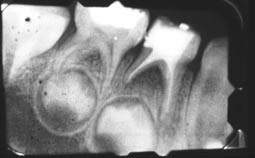

Fatem Zohra âgée de 5 ans s’est présentée au service avec des caries d’extension plus ou moins importantes sur toutes les molaires temporaires (Fig 1-2). La première séance a été consacrée à la familiarisation de l’enfant avec les instruments et à la motivation à l’hygiène bucco-dentaire. Un examen clinique et radiographique pendant cette séance a permis l’établissement du diagnostic et du plan de traitement.

Lors de la séance suivante, le quadrant mandibulaire droit a été traité avec pulpectomie au niveau de 84 nécrosée et cavité classe I profonde au niveau de 85 où la carie était juxta-pulpaire (Fig 4a-4b-4c-4d). Les restaurations coronaires étaient de type amalgame pour la 85 et coiffe pédodontique préformée pour la 84 (Fig 7a).